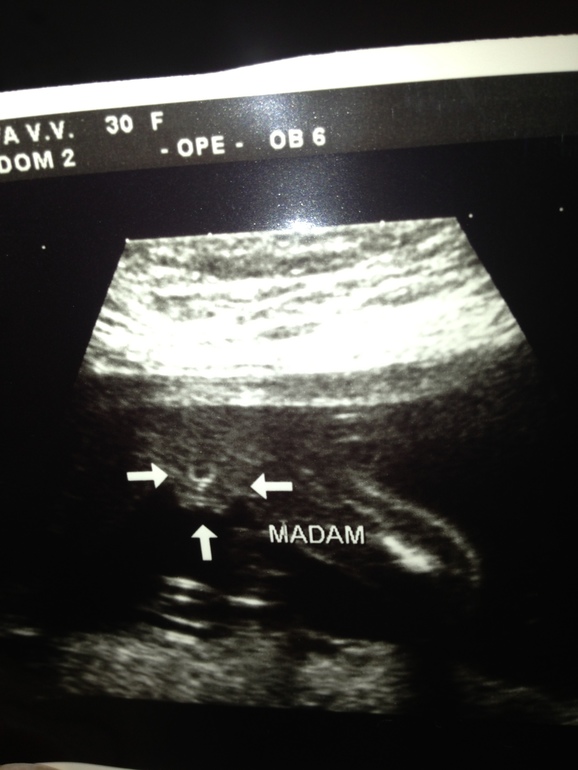

iren

Вот и раскрылась долгожданная интрига. А между стрелочками наша писюшка))). Честно говоря, мне не очень понятно, что это именно женский половой орган, но и мальчукового тоже ничего не видно. Врач сказал однозначно-девочка!